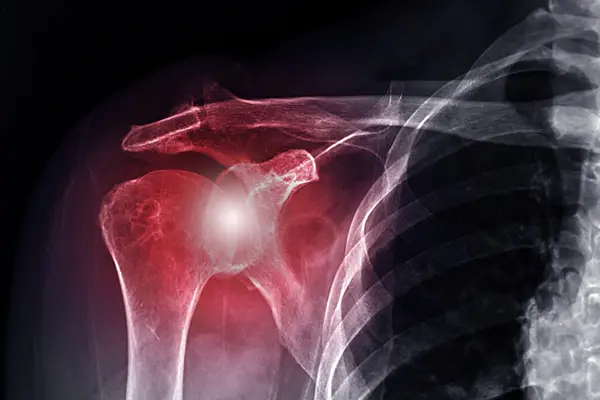

Shoulder instability is a painful and often disabling condition that occurs when the shoulder joint becomes loose or dislocates repeatedly. This happens due to tears in the labrum (the cartilage rim around the shoulder socket) or stretched ligaments. In young athletes and active individuals, instability can significantly affect performance and daily life.

Two of the most common surgical procedures to correct this are Bankart Repair and SLAP Repair. Both are performed arthroscopically using minimally invasive techniques. Bankart repair is usually recommended for patients with recurrent anterior shoulder dislocations, while SLAP repair targets superior labral tears, often seen in throwing athletes or those with overhead motion injuries.